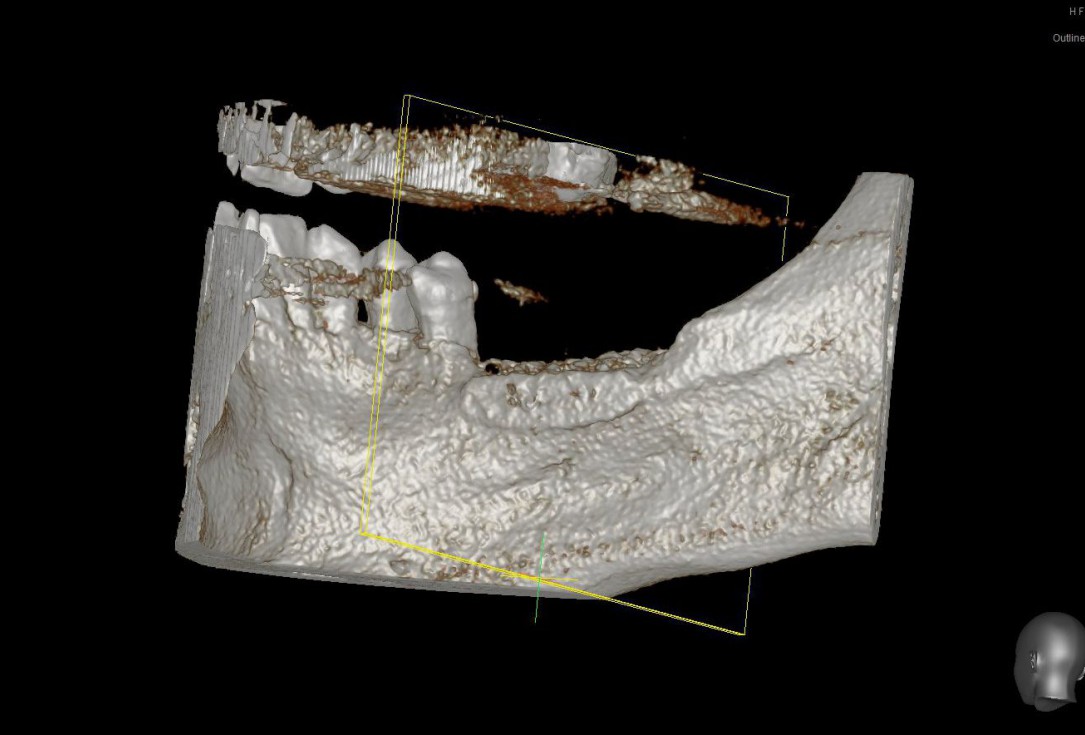

01/28 - Model of the initial defect computed from a CBCT scan - buccal viewThree-dimensional augmentation with maxgraft® cortico - Dr. R. Würdinger

02/28 - Model of the initial defect computed from a CBCT scan - lingual viewThree-dimensional augmentation with maxgraft® cortico - Dr. R. Würdinger

12/28 - Model of the augmented ridge before implantation computed from CBCT-recordings - buccal viewThree-dimensional augmentation with maxgraft® cortico - Dr. R. Würdinger

13/28 - Model of the augmented ridge before implantation computed from CBCT-recordings - lingual viewThree-dimensional augmentation with maxgraft® cortico - Dr. R. Würdinger

14/28 - Sagittal section of the alveolar ridge in the region of the defect before the augmentation and after 5 months of healing at implantationThree-dimensional augmentation with maxgraft® cortico - Dr. R. Würdinger